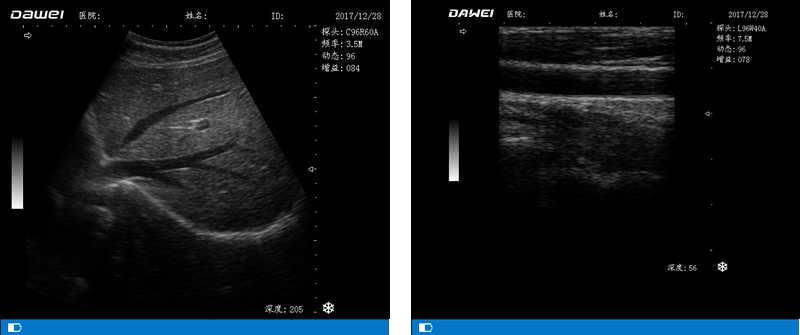

DW-500

筆記本全數字超聲診斷儀

高陣元 高清晰度 多功能

多倍率顯示 病變診斷更準確